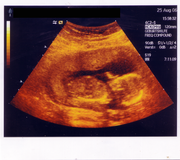

Sonografie

Ultrazvuk se dá použít třeba při lékařském vyšetření. Ultrazvukové vlny procházejí tělem a odrážejí se od jednotlivých orgánů resp. od přechodů mezi tkáněmi s různou akustickou impedancí.